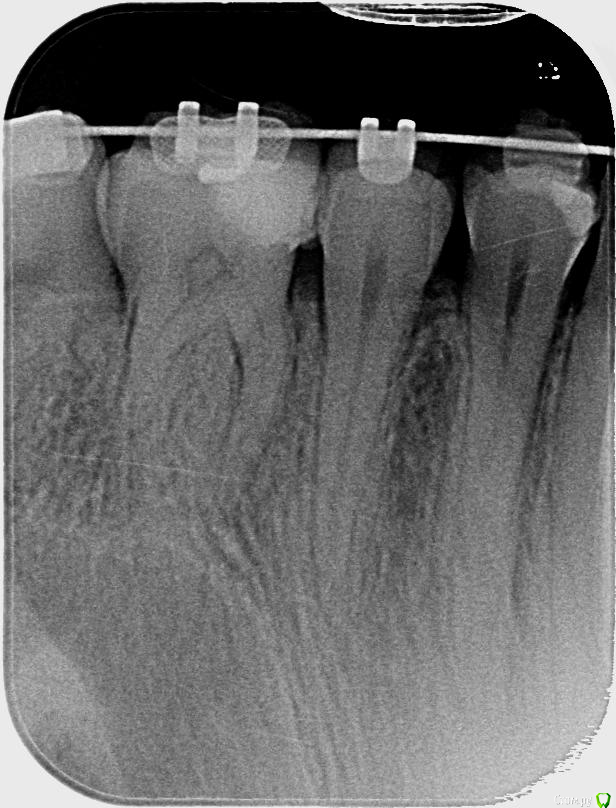

Axel_R Опубликовано 30 января, 2019 Поделиться Опубликовано 30 января, 2019 (изменено) Во рту стоят старые фотополимерные пломбы, им лет 5. Внешне они почти Ок. Как узнать есть ли кариес под пломбой (любой стадии), не снимая ее, не высверливая? Ни прицельный снимок, ни ортопанограмма кариес вроде как не показывают (ну или мой терапевт не умеет определить есть/нет по ним ), возможно КТ показывает или другое исследование или чудо-прибор)? Для чего нужно: если в результате выяснится, что кариеса под пломбами нет, так пусть себе стоят и дальше. А если под под ними кариес есть (и развивается... ) , то пойду поскорее заменю на новые. Снимок только 1, на нем:зуб 14 - пломбазуб 15 - пломбы нет, есть подозрение на кариес под эмалью (различима серая область если светить на зуб яркой лампой) Изменено 31 января, 2019 пользователем Axel_R Ссылка на комментарий

red_butler Опубликовано 31 января, 2019 Поделиться Опубликовано 31 января, 2019 4, 5 и 6 зубы нужно лечить 2 Ссылка на комментарий